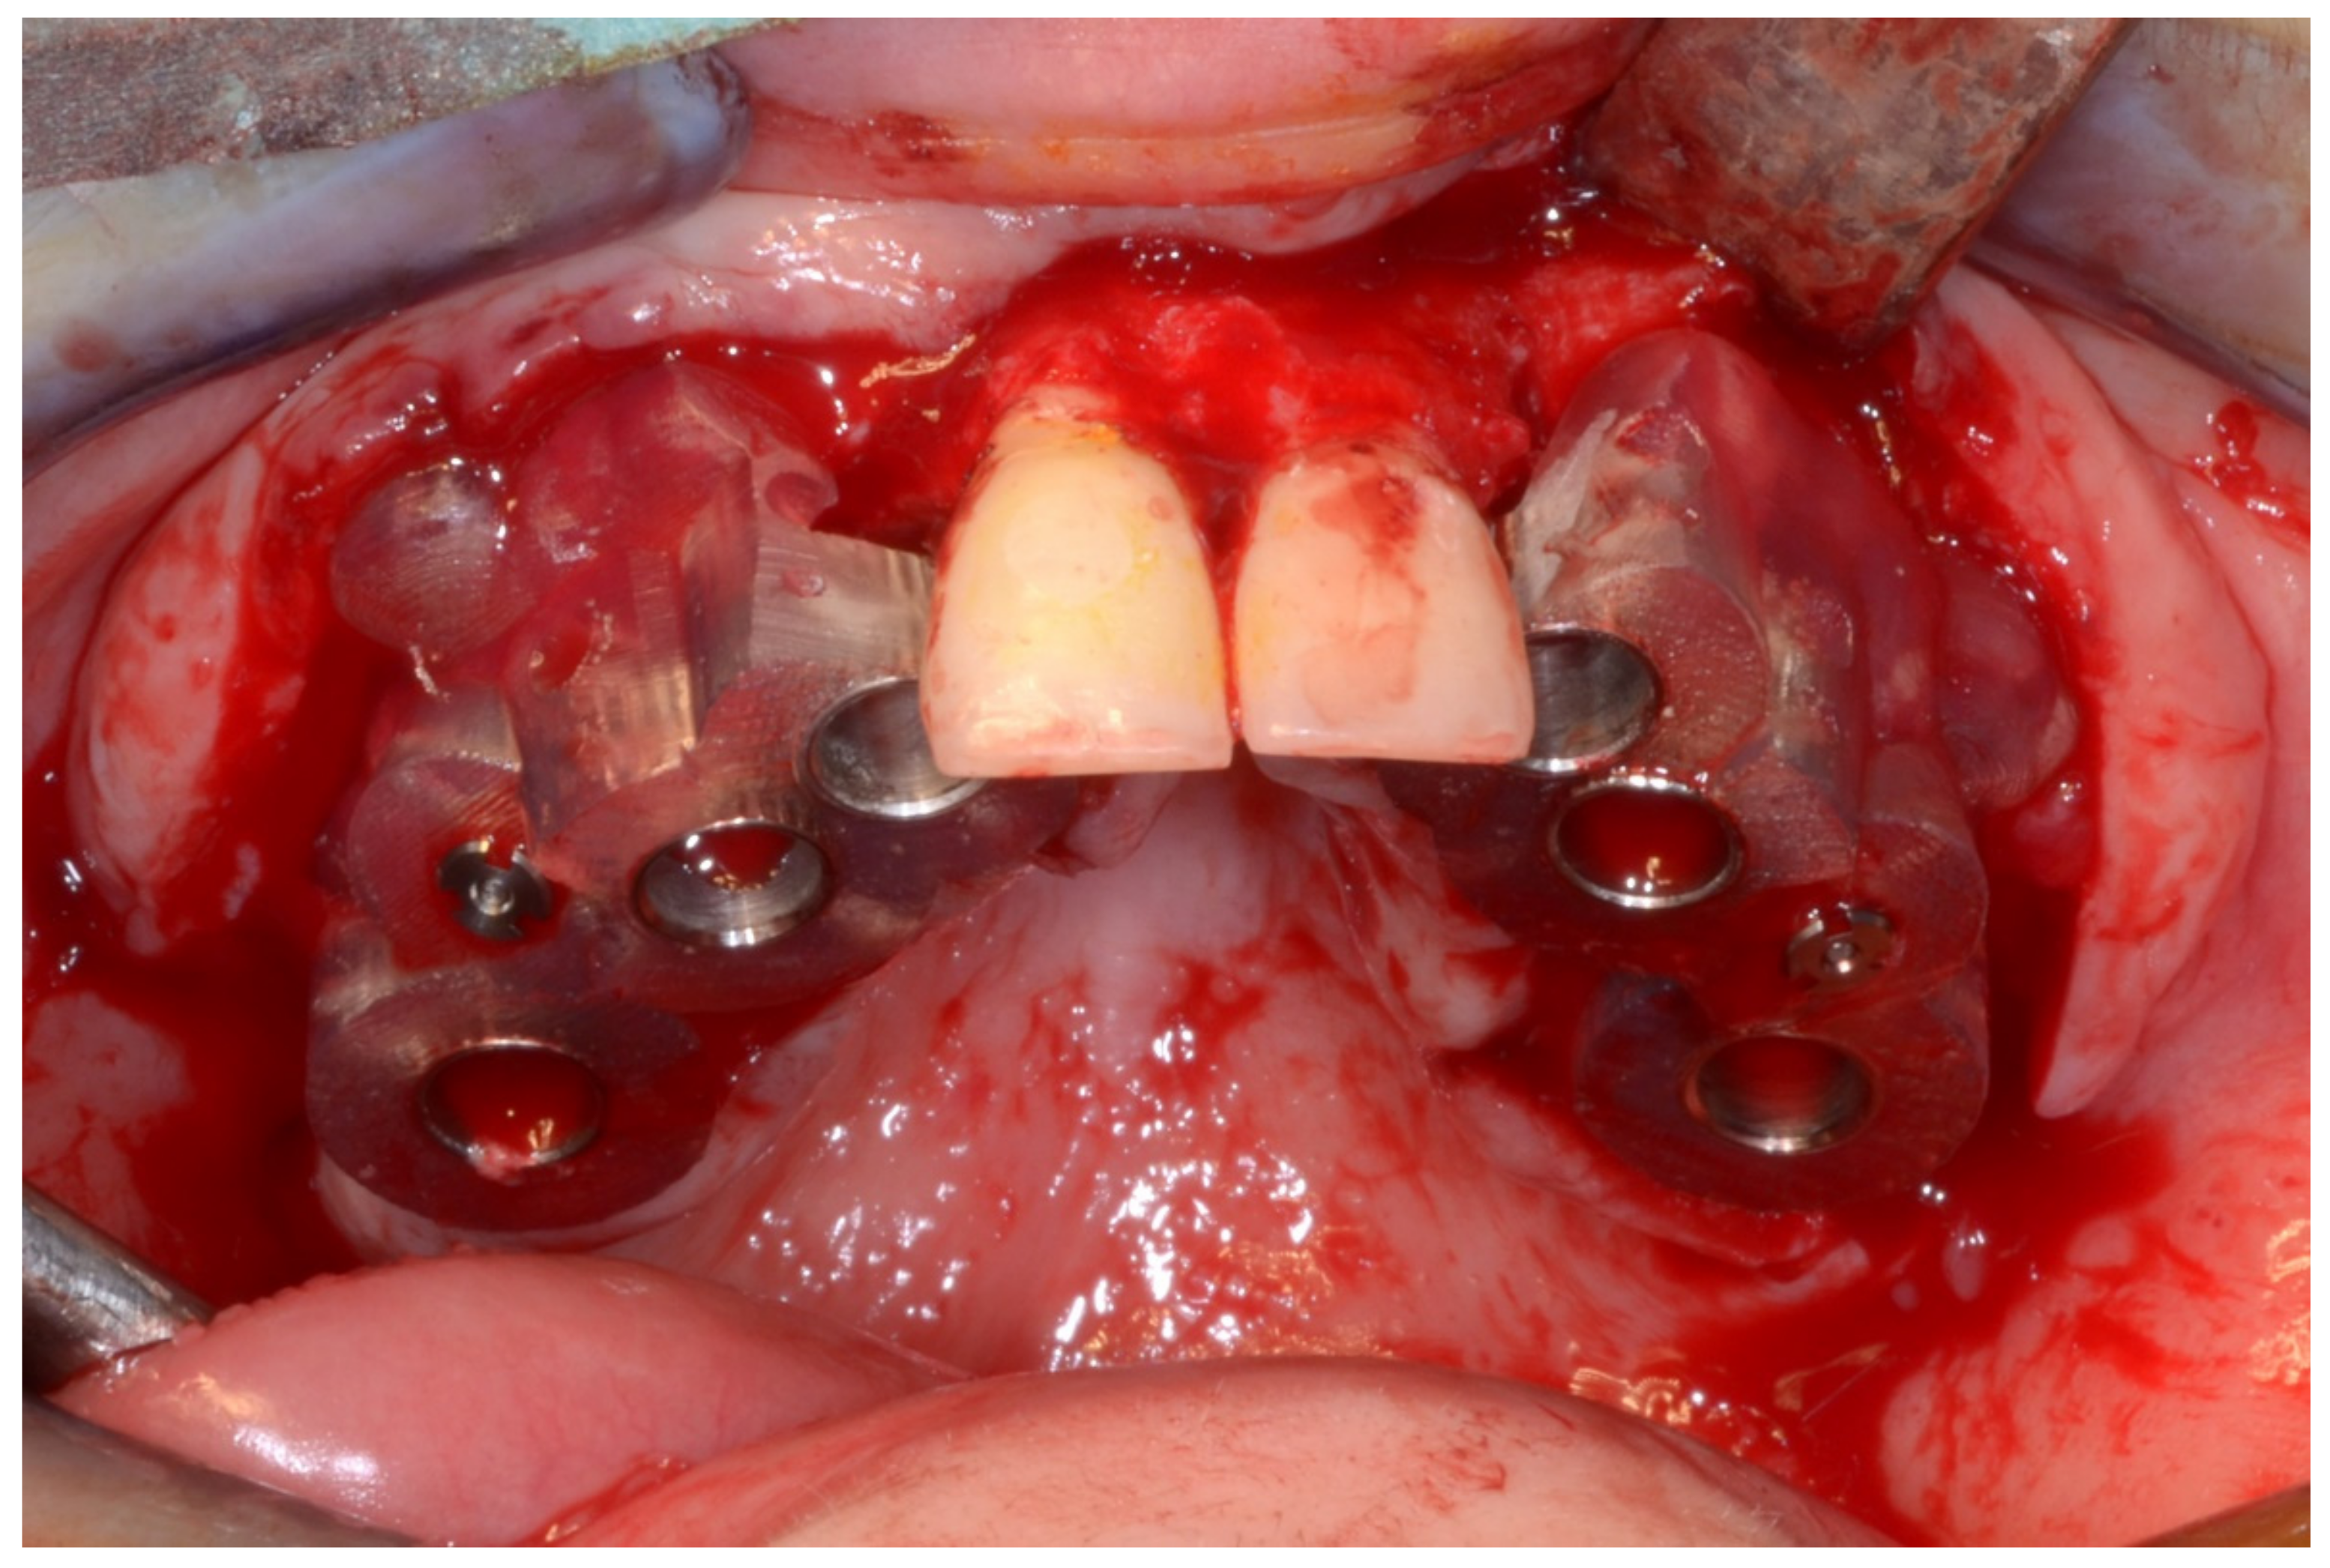

6.2.4. Intra-Operative Documentation:

6.3.4. Intra-Operative Documentation: